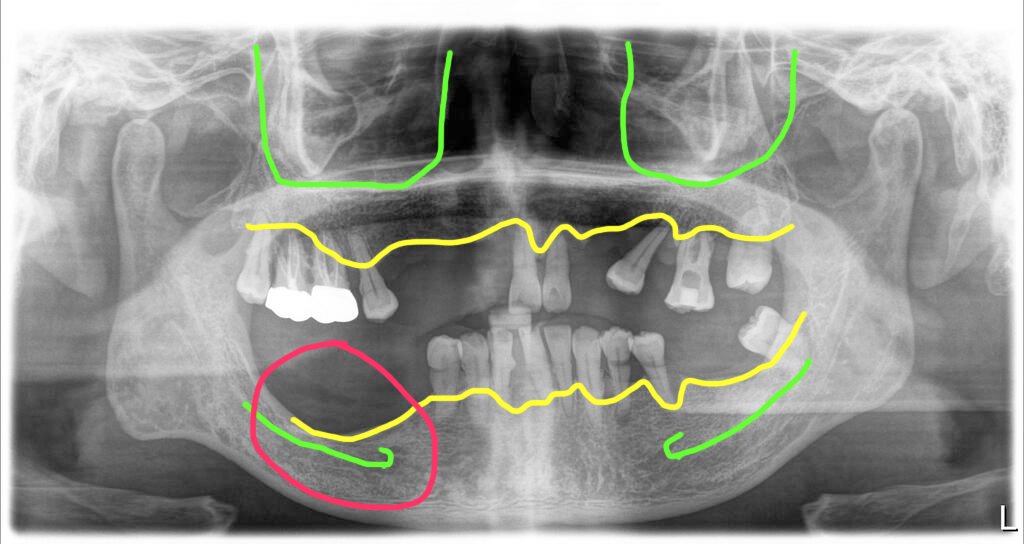

오늘 설명해 드릴 사례는 하악에 치조골이 너무 심하게 파괴되어 하악신경의 가지인 하치조신경과의 거리가 너무 가까워 해당 부위에 임플란트를 심지 않고 피해서 치료를 마무리한 경우입니다.

우측 아래 어금니 부위 자연발치로 신경 가까이까지 뼈파괴

위턱의 경우에는 임플란트를 식립하기에 충분한 뼈가 있었지만 오른쪽 아래턱 부위에는 뼈가 너무 심하게 내려앉아 신경부위 근처까지 파괴가 되어 있었습니다.

그래서 해당 부위에는 임플란트를 심지 않고 뼈가 있는 부위까지만 식립을 하기로 했습니다.

이렇게 심한 뼈파괴는 치주염이 진행된 치아를 그냥 방치해서 생기는 경우가 대부분입니다. 염증이 계속 진행되면서 뼈를 모두 녹여버리면 뼈이식도 불가능할 정도로 파괴가 일어나게 됩니다.

그래서 살릴 수 없다고 판단되는 치아는 적절한 시기에 발치를 해 주는 것이 아주 중요합니다. 그래야 뼈를 보호할 수 있습니다.